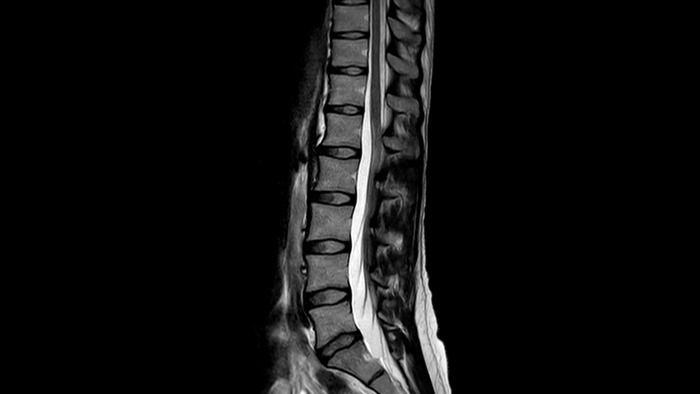

Affidabilità diagnostica Risoluzione spaziale fino al 60% più elevata, con lo stesso tempo di scansione.4

1 Anche nella remota eventualità che venga meno la tenuta ermetica del magnete, la fuoriuscita di una quantità trascurabile di elio non influirebbe in modo sostanziale sul livello di ossigeno presente nella sala. 2 Rispetto alle scansioni Philips senza Compressed SENSE. 3 Per una frequenza cardiaca bassa (50 bpm), rispetto alle scansioni Philips senza Compressed SENSE. 4 In scansioni 3D MSK VIEW isotropiche, rispetto alle scansioni Philips senza Compressed SENSE.